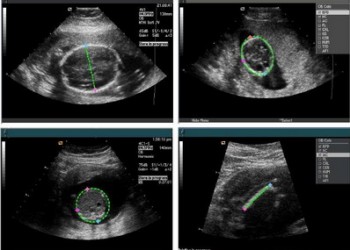

Iată care sunt principalii indici de biometrie fetală:

- DMS (diametrul mediu al sacului) = reprezintă media aritmetică a dimensiunilor craniocaudală, transversală și anteroposterioară a sacului gestațional și este utilizată pentru aprecierea vârstei gestaționale până la 5-6 săptămâni de amenoree; valoarea sa este de 2-3 mm la 4 săptămâni, 5 mm la 5 săptămâni și 15 mm la 6 săptămâni

- CRL (crown-rump length) = lungimea cap-șezut, este cel mai bun parametru care estimează vârsta gestațională în primul trimestru (după săptămâna 13, fătul se curbează și aprecierea vârstei gestaționale se face pe baza diametrului biparietal, BPD)

- BPD (biparietal diameter) = diametrul biparietal, este parametrul cu cea mai bună acuratețe în stabilirea vârstei gestaționale în trimestrul 2

- AC (abdominal circumference) = circumferința abdominală, prezintă o acuratețe maximă în corelarea cu vârsta gestațională între săptămânile 26-31

- FL (femoral length) = lungimea femurului

- HC (head circumference) = circumferința craniană

În momentul efectuării măsurătorilor, valorile sunt automat calculate de aparatul de ecografie și după compararea cu nomograme, afișează vârsta gestațională corespunzătoare valorii determinate.